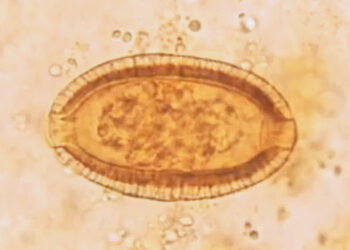

Read moreDetailsTítulo: Diagnóstico Parasitológico Autores: Carolina Carvalho dos Santos e João Felipe do Nascimento Sampaio O projeto Diagnóstico Parasitológico teve como objetivo...